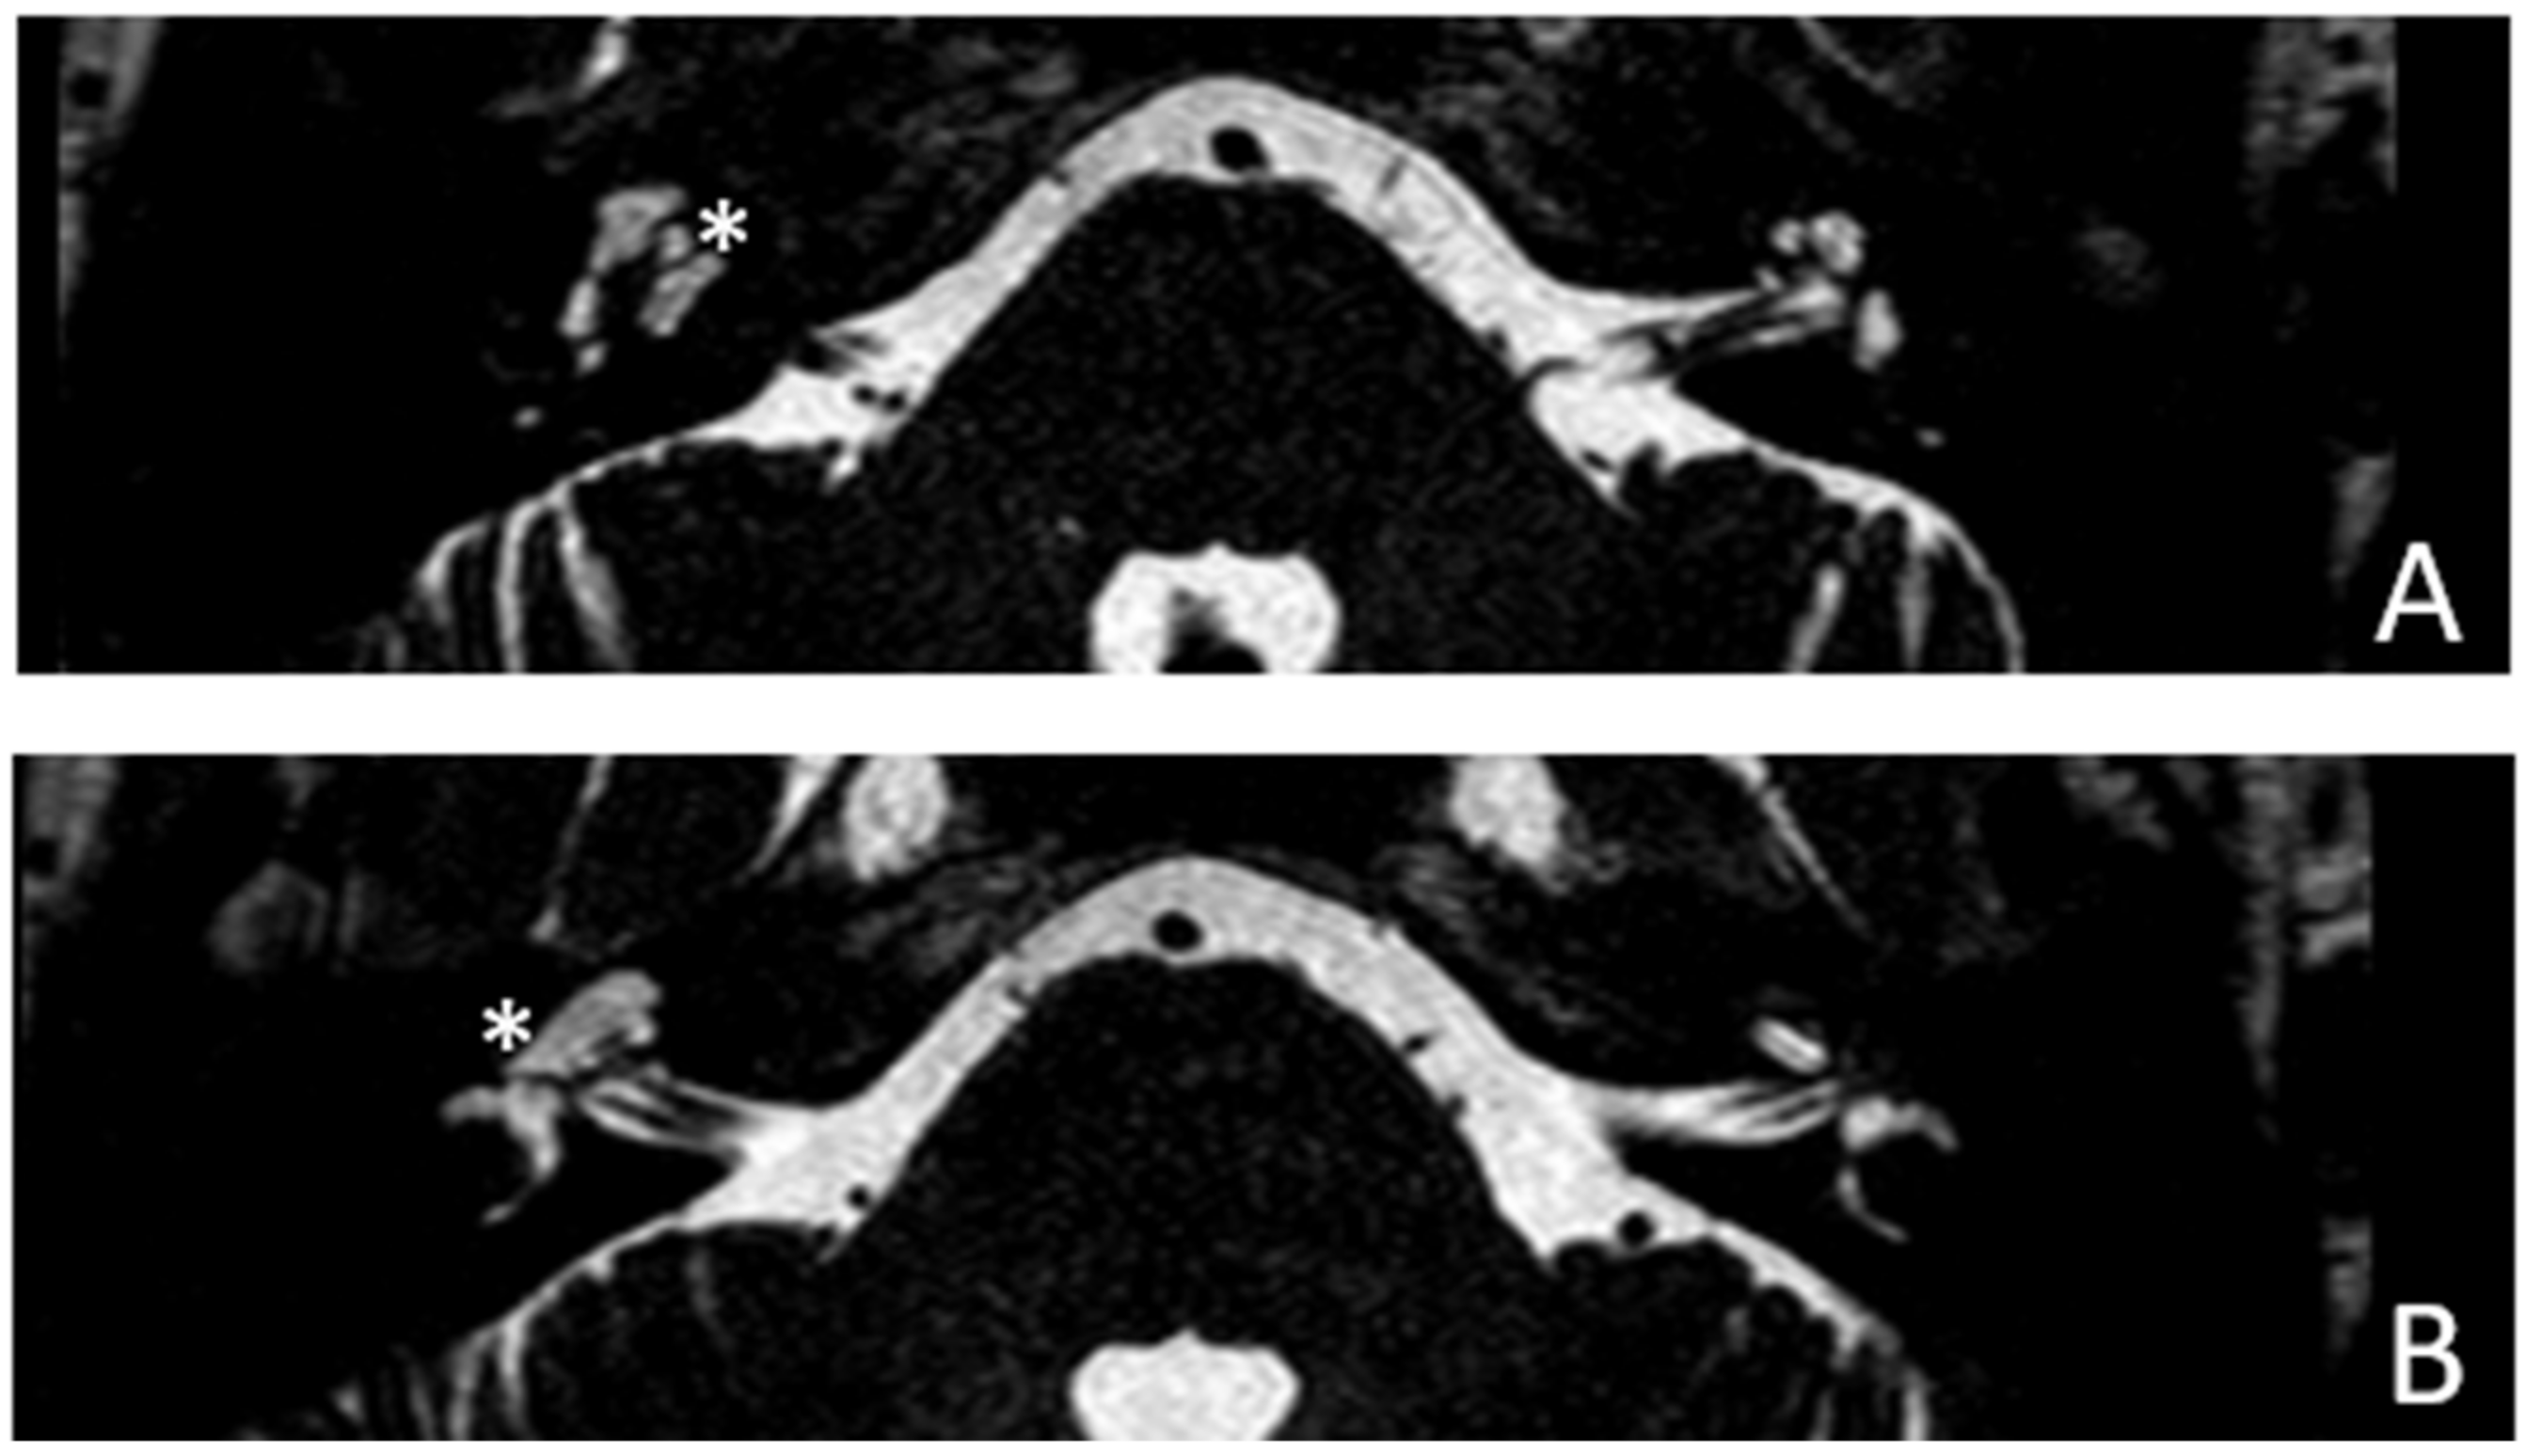

Patient #5, affected by otosclerosis: She developed mild CHL on the right ear at the age of 29 and then mild CHL on the left side at the age of 36. On the right she progressed to moderate MHL, but on the left she progressed to severe SNHL. On CT and MR images (Figure 9 and Figure 10), the otosclerotic lesions are well visible bilaterally, but only the right ear was included in the study because a cavity around the cochlea, communicating with the perilymph, was present only on the right side. The patient received a left cochlear implant 10 years after diagnosis.

Figure 9.

CT images of patient #5 with otosclerosis. (A,B), axial plane. The cavity around the cochlea is only visible on the right side (the circles indicate the contact of the osteorarefation with the cochlea), instead there is only an otosclerotic process without cavity on the left side.

Figure 10.

MR images of patient #5 with otosclerosis. MR cisternography. (A,B), axial plane. Note the presence of fluid signal in the newly formed cavity on the right side only (white asterisks).